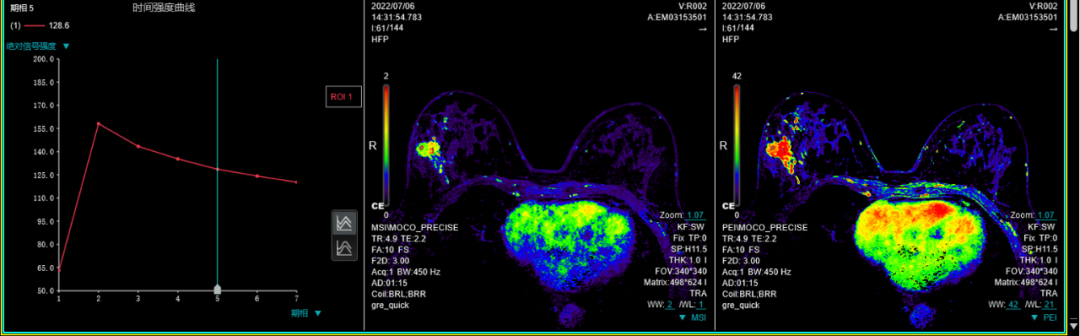

十、肝脏动脉期多期扫描技术(最多可达32期):此项检查技术主要应用于上腹部,尤其是应用于不同期相肝脏富血供肿瘤的检出上。

联影磁共振怎么样平原县第一人民医院联影uMR780 光梭3.0T磁共振正式投入使用,开启医学影像新时代!_https://www.jmylbn.com_新闻资讯_第27张

联影磁共振怎么样平原县第一人民医院联影uMR780 光梭3.0T磁共振正式投入使用,开启医学影像新时代!_https://www.jmylbn.com_新闻资讯_第28张